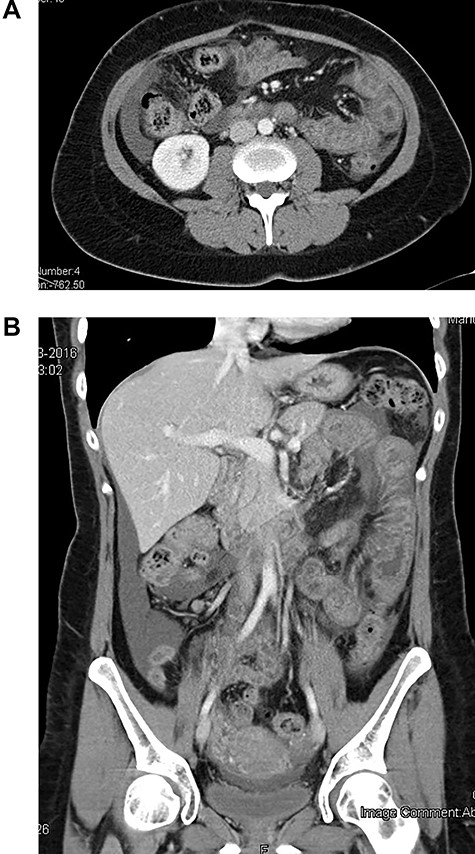

The patient was admitted hemodynamically stable and afebrile. Abdominal examination was concerning for the diffuse tenderness, guarding and rebound in the lower right quadrant. Laboratory analysis revealed leukocytosis 1646 × 103/μl with 1400 × 103/μl absolute neutrophils, urea and creatinine in normal values, c-reactive protein of 0.69 mg/dl. Abdominal computed tomography (CT) scan with contrast showed moderate volume of ascites and segmental jejunal wall thickening and stratification, with edematous hypoattenuating submucosa, mucosa and muscularis propria enhancement (‘target sign’). No lymphadenopathy was identified and the mesenteric vessels were patent. The solid organs were normal and no free air was detected (Fig. 1). Due to severe abdominal pain, resembling an acute abdomen, we decided to perform an emergency diagnostic laparoscopy that showed only free serous intra-abdominal fluid in all quadrants of the abdomen, a mild erythema and edema of the small bowel. The fluid was aspirated and a prophylactic appendicectomy was performed. The patient was discharged on the third postoperative day. Microbiology of peritoneal fluid was negative.

CT scan at initial clinical presentation (A—coronal plane; B—axial plane)—moderated distended small bowel loop with diffuse circumferential wall thickening, submucosa edema (‘target sign’) and shaggy luminal contour. Moderate amount of ascites in peritoneal cavity is also noted.